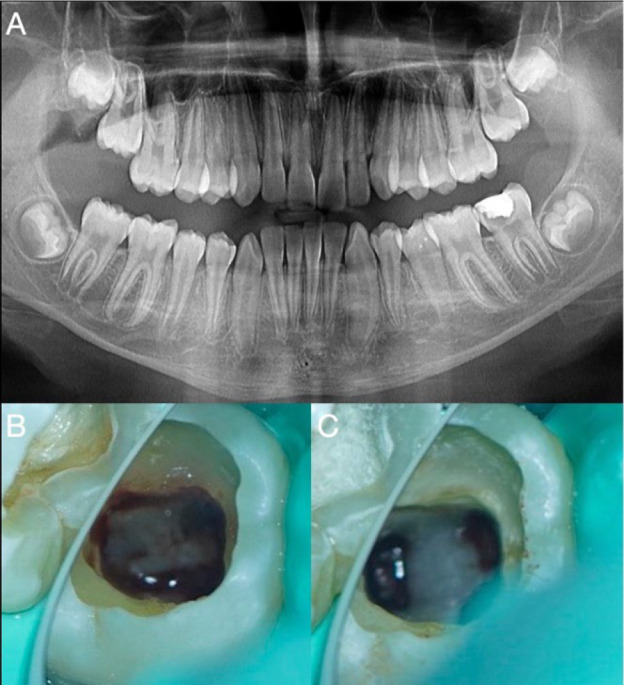

Vital pulp therapy is one of the least invasive and simplest and most economically acceptable treatment alternatives for immature teeth with pulpitis. The success rate of this treatment, with calcium silicate-based cements, ranges from 85% to 100%. Vital pulp therapy prevents the development of apical periodontitis and promotes normal root development, allowing the tooth to remain in the dentition and perform its functions. The patient was a nine-year-old boy with pain on chewing and a positive response to cold. The panoramic radiograph showed an immature permanent lower molar with deep caries. Partial pulpectomy and root pulp sealing with pre-mixed calcium silicate-based cement were performed under aseptic conditions. The absence of symptoms and the formation of roots with apical sealing were successfully achieved and observed by follow-up and radiographic control, making this treatment a viable option for immature teeth with pulpitis.